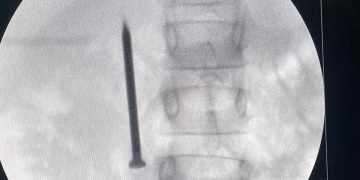

أعلن الدكتور أحمد القاصد، رئيس جامعة المنوفية، عن نجاح فريق طبي متخصص بوحدة مناظير الجهاز الهضمي بمعهد الكبد القومي في إنقاذ حياة طفلة تبلغ من العمر “7 سنوات”، بعد ابتلاعها مسمارًا معدنيًا حادًا يبلغ طوله 4 سنتيمترات.

أوضح رئيس الجامعة،أن الفريق الطبي تمكن من استخراج المسمار الذي وصل إلى الجزء الأول من الأمعاء الدقيقة (الصائم) عبر إجراء منظار طارئ لم يستغرق سوى 20 دقيقة، متجنبًا بذلك خطر الثقب أو النزيف أو الانسداد المعوي الوشيك، و غادرت الطفلة المستشفى بصحة جيدة بعد التدخل الطبي السريع.